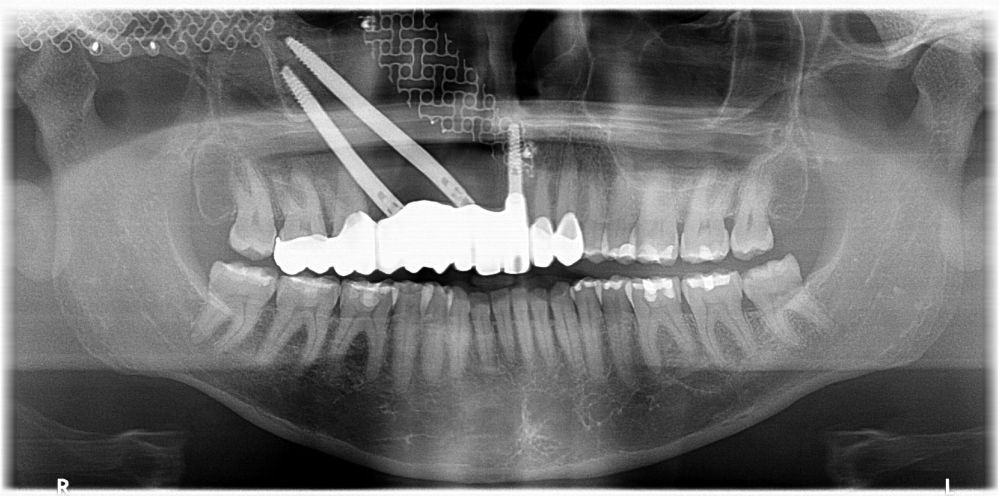

Bajo anestesia general, se realizó la resección quirúrgica junto con la fijación de dos placas preformadas y colocación simultánea de dos implantes cigomáticos y un implante endoóseo en posición del 2.1 (Figuras 5 y 6). Debido a la presencia de márgenes quirúrgicos comprometidos en el informe anatomopatológico, se indicó la administración de radioterapia adyuvante. Por este motivo, se decidió realizar un puente provisional dentosoportado de 1.7 a 2.3 (Figura 7) para mejorar la situación estética y funcional de la paciente durante todo el proceso y evitar un colapso de los tejidos blandos por la radioterapia. Para ello, se tallaron los molares (1.7, 1.6) e incisivo lateral y canino (2.2, 2.3), y se fabricó un puente fresado en polimetilmetacrilato (PMMA) con refuerzo metálico (Figuras 8 y 9).

Al mes de la intervención, la paciente comenzó con la radioterapia. El protocolo de radioterapia adyuvante fueron 30 sesiones.

Una vez finalizada la radioterapia, la paciente se encontraba libre de enfermedad. Por lo que se procedió a la restauración definitiva implantosoportada. Tras la segunda fase, se colocaron dos pilares transepiteliales Multiunit Ò rectos y un pilar Multunit Ò angulado de 17º (Figura 10).